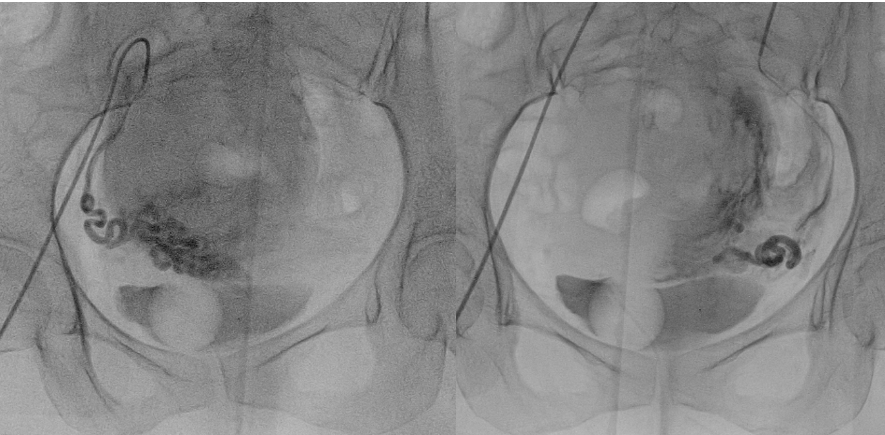

通过磁共振检查与妇检病理排除其他恶性疾病,胡女士适合进行介入微创栓塞保留子宫的治疗方法治疗,经过右腿打针超选择栓塞子宫腺肌症的营养血管,胡女士的子宫腺肌症血供丰富、生长旺盛,双侧子宫动脉供血(如下图)。